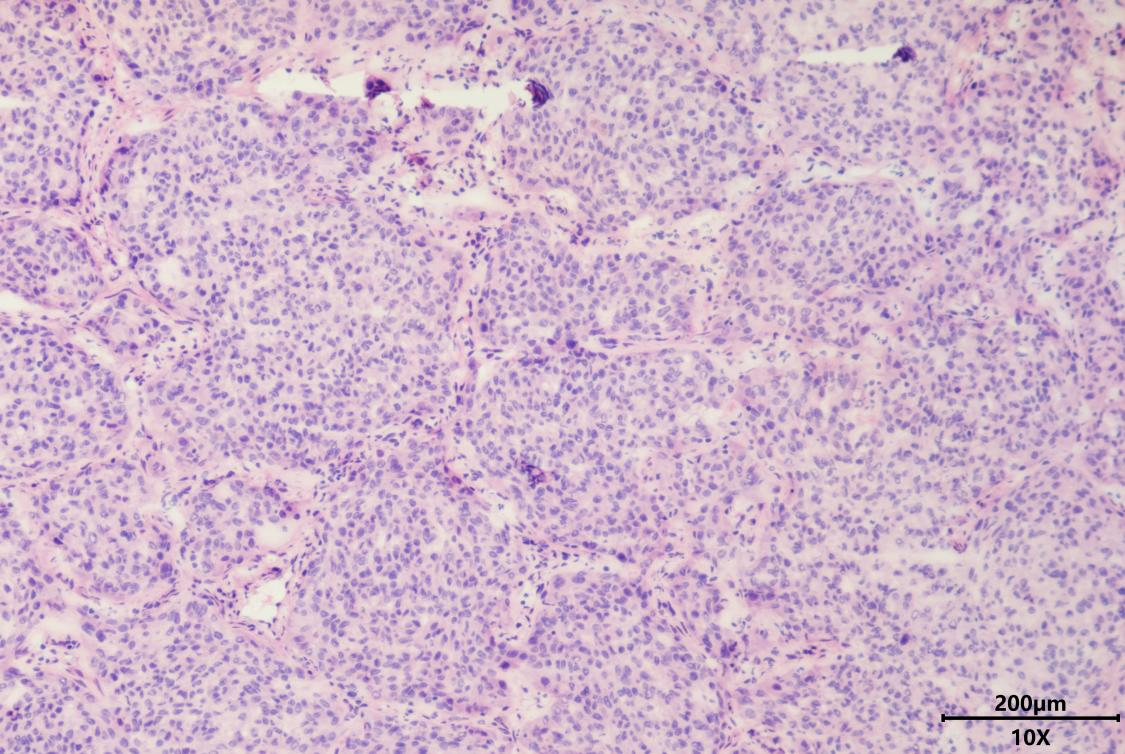

肺神经内分泌瘤术中冰冻HE染色